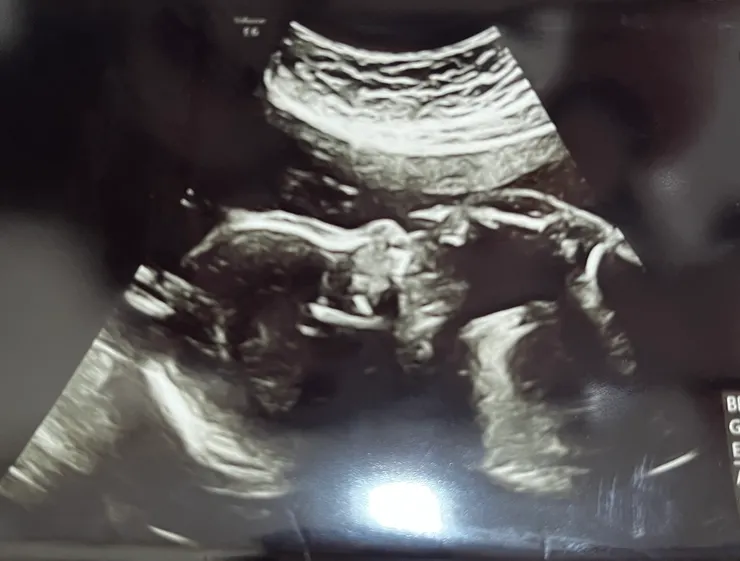

孕期中拍攝的超音波:腳放到臉上